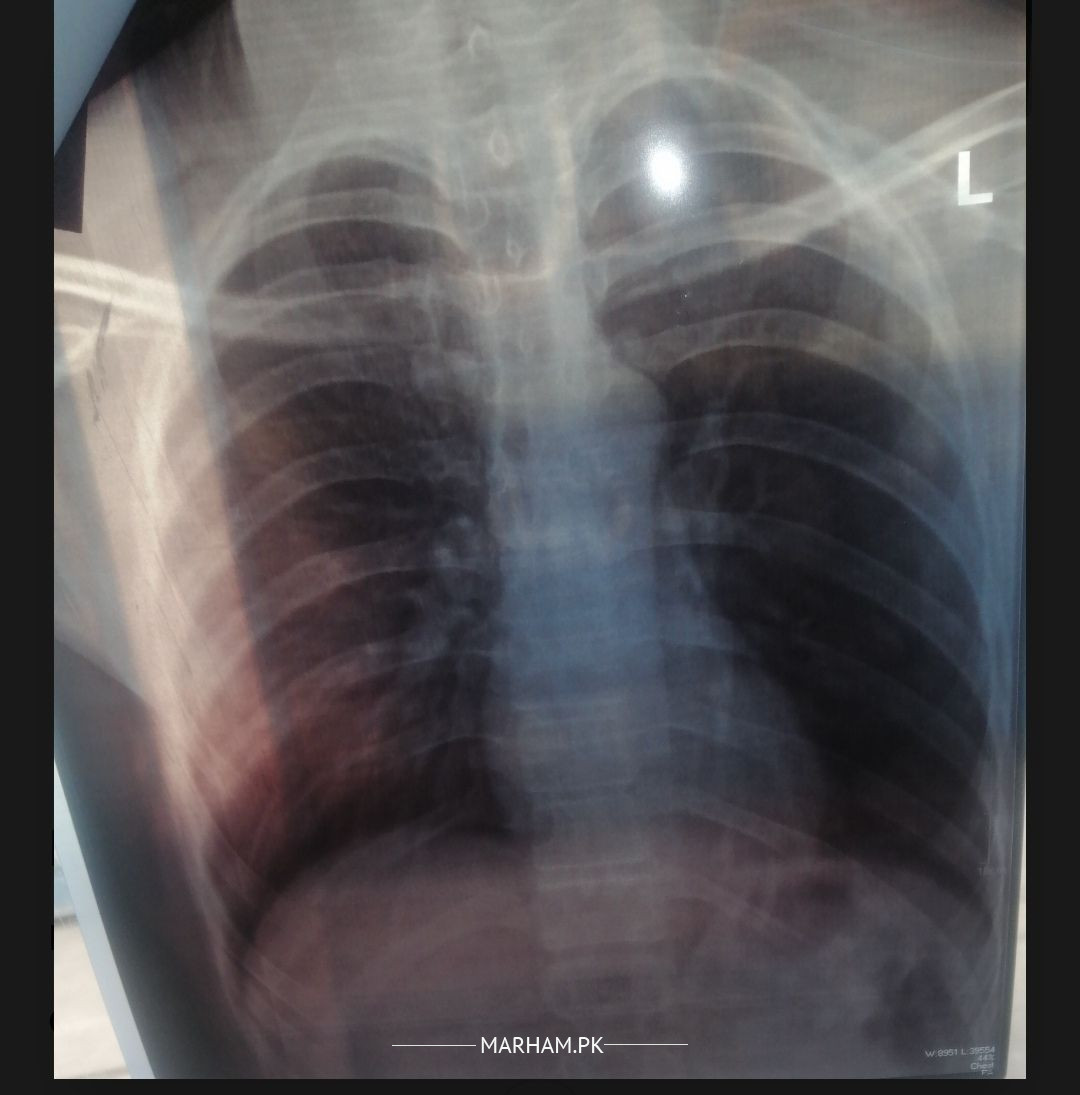

Asking For Self, Male 31, Mansehra

8 years smoking and no symptoms, general routine xray

Early signs of COPD.

looks normal, mild hyperinflation

Asalam Alaikum. If no symptoms then why you did XRay chest? I suggest to quit smoking as it is harmful for the health. If you have respiratory symptoms kindly visit your nearest chest physician at any government or private hospital.

NORMAL.